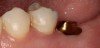

Plugging into digital workflows provides opportunities to integrate CAD/CAM technologies at every step of the treatment process for dental implants. In another example, a patient presented with a failing tooth No. 8 (Figure 6 and Figure 7). After discussing treatment options, the patient chose to forgo any treatment to address tooth and soft-tissue asymmetries and wanted to proceed with a dental implant-supported restoration without additional treatment. After integrated 3-dimensional planning, the tooth was extracted, and then an implant and the final custom CAD/CAM abutment (titanium base with zirconia supra-structure) were placed with a provisional restoration in the same visit (Figure 8 and Figure 9). Soft-tissue grafting was also done at the same visit to address the deficient buccal tissue height on No. 8 (Figure 10). At 3 months, the patient presented for the final restoration, with excellent healing around the implant (Figure 11) and soft-tissue healing guided by the custom abutment (Figure 12).

Fig 6. Clinical presentation of patient with a failing tooth No. 8.

Figure 6

Fig 7. Preoperative radiograph showing previous endodontic therapy on tooth No. 8.

Figure 7